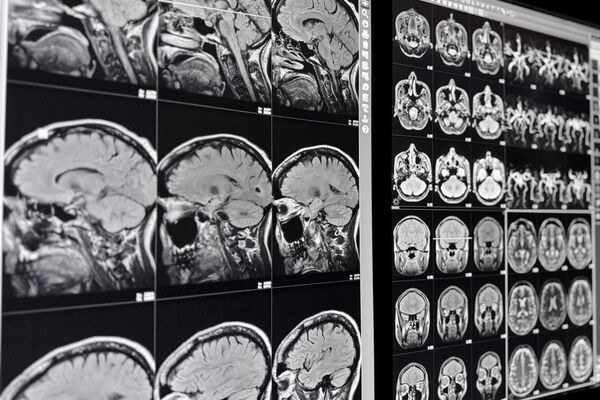

Die Magnetresonanztomograhie (MRT) ist ein bildgebendes Verfahren, das Gewebe exakt abbildet – vollkommen strahlungsfrei.

Mit diesem Verfahren, auch Kernspintomographie genannt, sind wir in der Lage, aussagekräftige Schnittbilder sämtlicher Körperregionen zu erstellen. Dabei wird die MRT als hochaussagekräftiges diagnostisches Verfahren heute routinemäßig bei verschiedensten Fragestellungen eingesetzt.

Dank des enormen technischen Fortschritts der MRT-Forschung, insbesondere der MR-Gradiententechnik und der Herstellung von organspezifischem Kontrastmittel, ist es uns heute möglich, den gesamten menschlichen Körper darzustellen – und dies nicht-invasiv, also ohne Eindringen in den Körper.